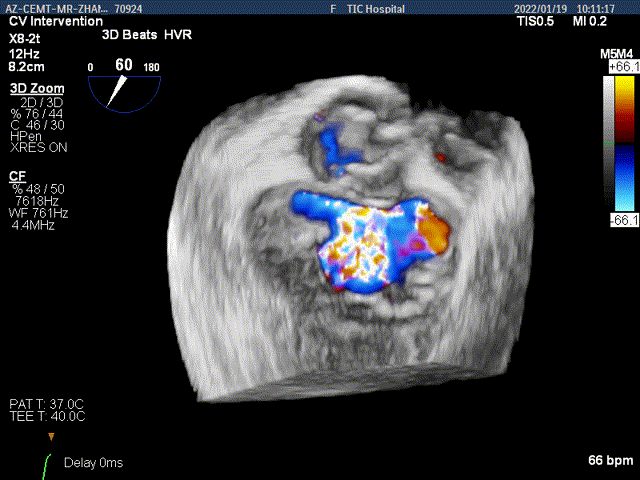

3D-color MV view:大量反流,起源于2区

Color-view:大量反流,主要血流PISA来源于2区

3D视图下夹子对准最大反流束进入左室